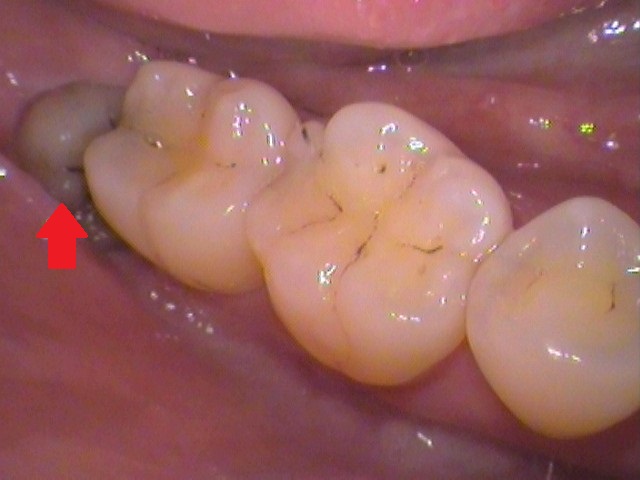

お口の中を見てみると、

このような状態。

親知らずがひょっこり顔を出しているのが分かりますね。

ここです。